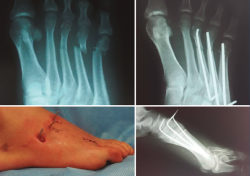

Figura 4. Octavo paciente objeto de nuestro estudio, femenino, de 60 años, quien sufre fractura en 5.º metatarsiano por traumatismo indirecto en caída por motocicleta. En sentido horario empezando arriba a la izquierda: imagen fluoroscópica lateral al finalizar el procedimiento quirúrgico, radiografía preoperatoria, fijación interna anterógrada con doble alambre de Kirschner de 1,5 mm y aspecto del pie al finalizar el procedimiento quirúrgico.

En las Figuras 3 y 4 se presentan los resultados postoperatorios de los pacientes incluidos en nuestro estudio.